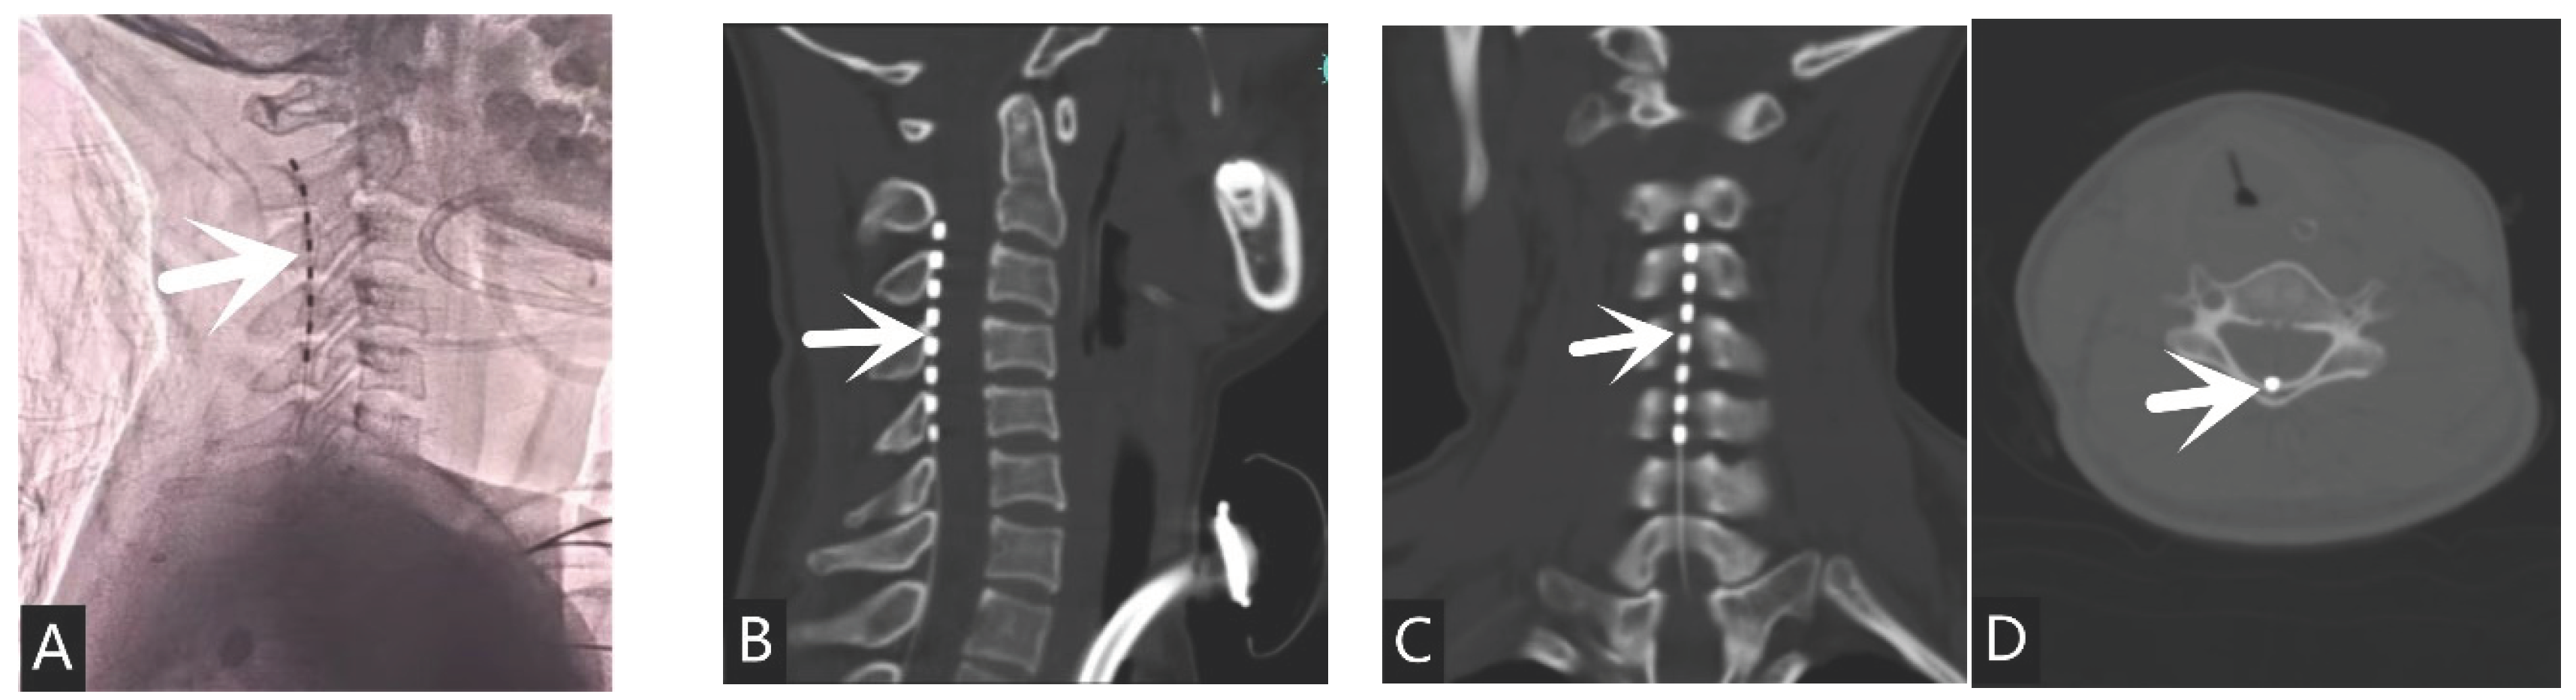

The target of DBS surgery is the bilateral thalamic central midline parafascicular nucleus (CM-pf nucleus). If electrodes cannot be placed on one side due to skull repair or other reasons, only the other side can be placed, and it can be placed on the same side as the ventricular shunt tube (Figure 1). The electrode placement site for spinal cord electrical stimulation is on the dorsal side of the epidural layer at the level of 2-3th in the neck(Figure 2).

Figure 1. A stroke patient with secondary hydrocephalus underwent VPS and DBS surgery: (A) Placement of left DBS (white arrow)and right ventricular shunt(black arrow) simultaneously during surgery; (B) Fusion of CT and MRI images before DBS surgery, locating the left CM-pf nucleus(white arrow); (C) The end of the DBS electrode is located in the left CM-pf nucleus region(white arrow).